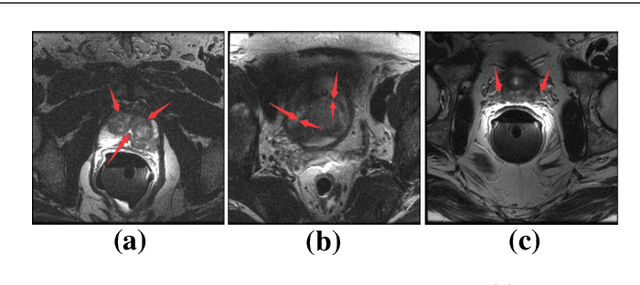

Abstract:Accurate segmentation of the prostate from magnetic resonance (MR) images provides useful information for prostate cancer diagnosis and treatment. However, automated prostate segmentation from 3D MR images still faces several challenges. For instance, a lack of clear edge between the prostate and other anatomical structures makes it challenging to accurately extract the boundaries. The complex background texture and large variation in size, shape and intensity distribution of the prostate itself make segmentation even further complicated. With deep learning, especially convolutional neural networks (CNNs), emerging as commonly used methods for medical image segmentation, the difficulty in obtaining large number of annotated medical images for training CNNs has become much more pronounced that ever before. Since large-scale dataset is one of the critical components for the success of deep learning, lack of sufficient training data makes it difficult to fully train complex CNNs. To tackle the above challenges, in this paper, we propose a boundary-weighted domain adaptive neural network (BOWDA-Net). To make the network more sensitive to the boundaries during segmentation, a boundary-weighted segmentation loss (BWL) is proposed. Furthermore, an advanced boundary-weighted transfer leaning approach is introduced to address the problem of small medical imaging datasets. We evaluate our proposed model on the publicly available MICCAI 2012 Prostate MR Image Segmentation (PROMISE12) challenge dataset. Our experimental results demonstrate that the proposed model is more sensitive to boundary information and outperformed other state-of-the-art methods.

Abstract:Prostate segmentation from Magnetic Resonance (MR) images plays an important role in image guided interven- tion. However, the lack of clear boundary specifically at the apex and base, and huge variation of shape and texture between the images from different patients make the task very challenging. To overcome these problems, in this paper, we propose a deeply supervised convolutional neural network (CNN) utilizing the convolutional information to accurately segment the prostate from MR images. The proposed model can effectively detect the prostate region with additional deeply supervised layers compared with other approaches. Since some information will be abandoned after convolution, it is necessary to pass the features extracted from early stages to later stages. The experimental results show that significant segmentation accuracy improvement has been achieved by our proposed method compared to other reported approaches.